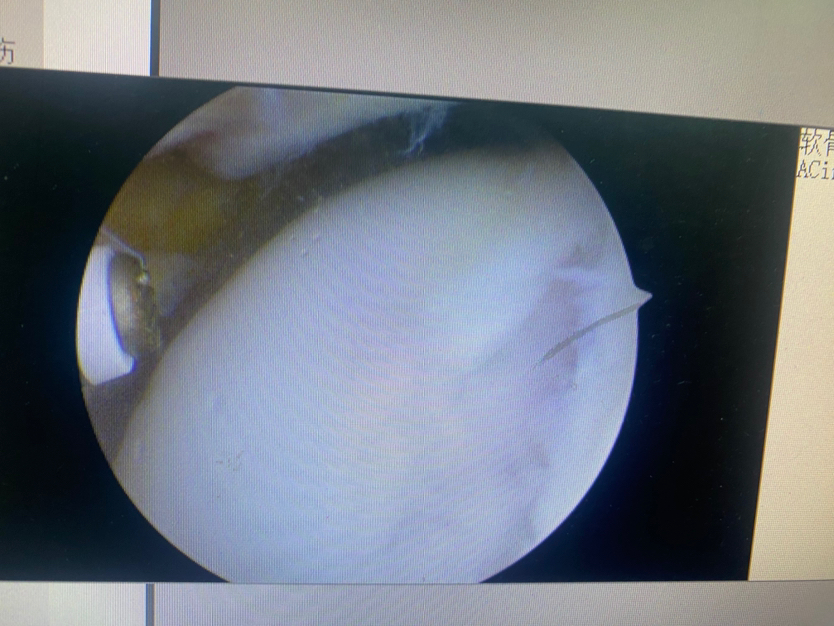

注射凝胶支架覆盖软骨损伤区

软骨修复后(完全覆盖填充)